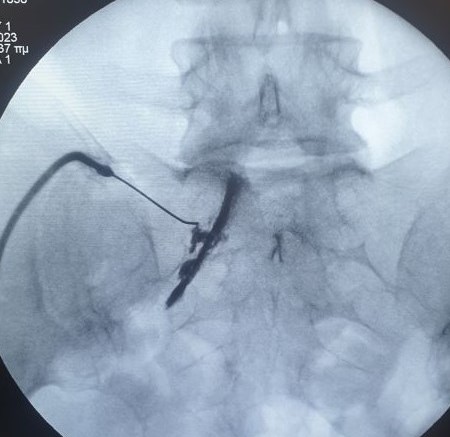

- Διέγερση της ρίζας με παλμική ραδιοσυχνότητα σε περιπτώσεις μετεγχειρητικής ισχιαλγίας

- Δισκοπλαστική με χρήση laser